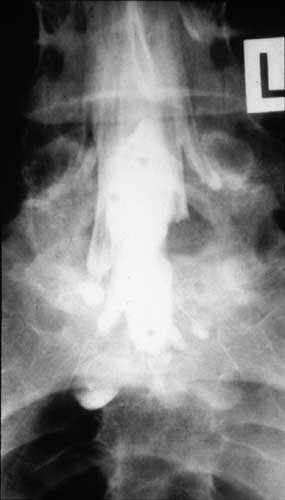

Abb: rechts, in der Myelographie